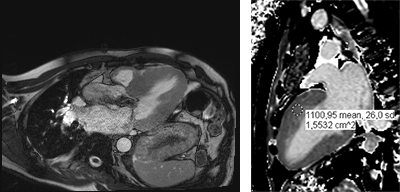

L’imagerie par résonance magnétique (IRM) est une technique radiologique qui utilise des ondes électromagnétiques. Elle permet une analyse très fine du cœur. C’est une technique d’imagerie très performante, indolore et sans danger, qui n’utilise pas de rayons X.

L’IRM donne à la fois des informations sur l’anatomie du cœur (taille d’un infarctus, maladies du muscle cardiaque) et sur son fonctionnement.